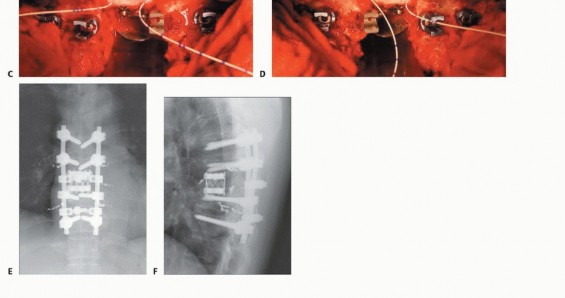

TECH FIG 6. A. A vertebral spacer is properly inserted to the anchor holes within the remaining healthy vertebrae. B. Schema of reconstruction (lateral view). C,D. After checking the appropriate position of the vertebral spacer radiographically, the posterior instrumentation is adjusted to slightly compress (10 mm in this case) the inserted vertebral spacer. E,F. Postoperative radiograph after spinal column shortening shows three pairs of preoperative embolization coils. (continued...)

TECH FIG 6. (continued...) G-I. Resection of two vertebrae. G. Bilateral artificial pedicles are placed. H,I. Postoperative radiographs of reconstruction with artificial pedicle.